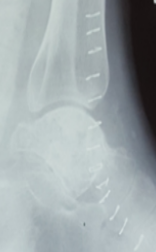

His X-ray of the left ankle joint [Figure 1(a)] revealed lytic lesion of the talus with some sclerotic changes with normal joint space. Hence, for further evaluation, we plan to go for computed tomography (CT) scan to define the lesion. His CT scan the left ankle [Figures 1(b-d)] revealed expanding lytic lesion of the talus involving dome, mid and posterior portion with cortical breach measuring 44*41 mm in size with intact ankle joint. Being CT scan was inconclusive, we plan to workup with magnetic resonance imaging left ankle [Figures 1 (e,f)] which showed multiloculated well-defined lesion of varying sizes in talus showing T1 hypointensity and T2 hyperintensity giving fluid-fluid level appearance suggestive of ABC.

Pre-operative lateral view of X-ray left ankle revealed lytic lesion with minimal sclerotic changes in talus. On further work-up with CT scan showed expanding lytic lesion of talus extending dome mid and posterior portion of talus with cortical breach (44*41mm) with intact ankle joint space. On pre-operative MRI there was multiloculated well defined lesion in talus showing T1 hypointensity and T2 hyperintensity suggesting ABC.

Before going to definitive management, we plan to go for biopsy of the lesion and histopathological examination (HPE) report of biopsy specimen showed necrotic bony fragment with fibrofatty tissue and occasional osteoclastic type of giant cells. Keeping the diagnosis as ABC of talus, we plan to go for curettage [Figure 2] and bone graft from iliac crest mixed with bone cement, based on recent management protocol for ABC of talus. Later in post-operative period, the final HPE of curettage specimen revealed cystic spaces with blood-filled cysts, at places lined with giant cells, finding consistent with ABC.